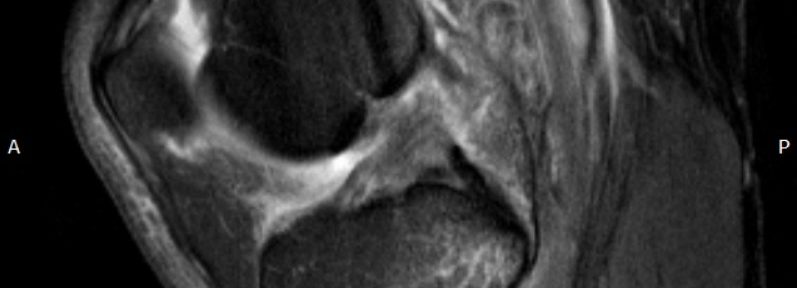

MRI #1 (April 1, 2023)

- Ihara classification: Type II by 1 radiologist; Type III by 2 radiologists → Majority: Type III (complete rupture with displaced stumps predominant)

MRI #2 (July 28, 2023)

- ACLOAS: Grade 1 (adequate thickness with restored continuity)

- Outcome: Initially a complete rupture with displacement (Ihara III), which progressed over several months on MRI to restored continuity with adequate thickness (ACLOAS 1)